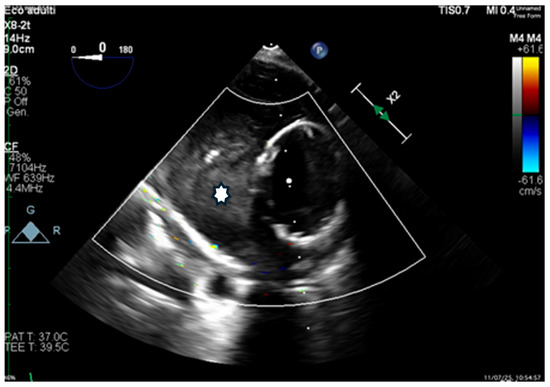

Transesophageal echocardiography (TEE) confirmed rapid thrombosis of the FL (Figure 7).

Figure 7.

Transesophageal echocardiography (TEE), transverse view, showing the Terumo Aortic endograft in the true lumen and the FLOD within the false lumen, with in situ thrombosis (*).